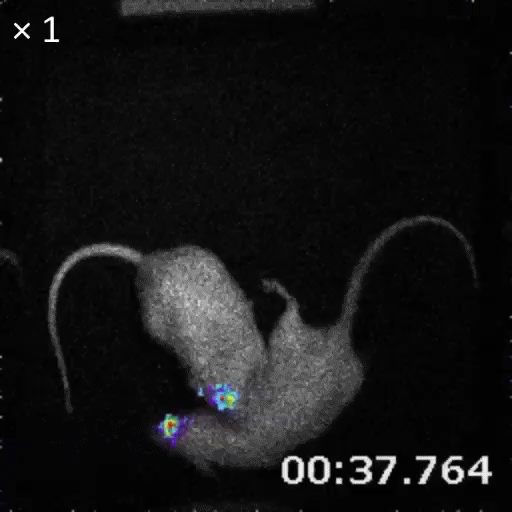

Glowing creatures like fireflies and jellyfish are captivating to look at but also a boon for science, as their bioluminescent molecules contribute to visualizing a host of biological processes. Now, scientists in Japan have supercharged these molecules, making them hundreds of times brighter in deep tissues and allowing for imaging of cells from outside the body. The bioengineered light source was used to track cancer cells in mice and brain-cell activity in monkeys, but its applications extend beyond the lab.

Based on previous work, the researchers knew that a synthetic luciferin called AkaLumine-HCl is able to penetrate the blood-brain barrier and produce a reddish light that is more easily seen in body tissues. It was not very compatible with the natural luciferase, however, so they successively mutated the enzyme to improve pairing with AkaLumine-HCl. The resulting Akaluc protein is both a more efficient catalyst for the substrate and more abundantly expressed by cells. In the mouse brain, this combination of Akaluc catalyzing AkaLumine-HCl, dubbed AkaBLI, resulted in a bioluminescence signal 1000 times stronger than that from the natural luciferase-luciferin reaction. Elsewhere in the body, just one or two glowing cells were clearly visible from within the mouse lung, something that could be useful for monitoring transplanted cells.

Bioluminescence can be introduced easily and voluntarily by including AkaBLI in animals' drinking water, which gives the most persistent glow, although injecting the molecules yielded greater intensity. "The fundamental improvement, though, is the practical applicability for in vivo physiological studies," says Miyawaki. With AkaBLI, how brain activity and structures change with behavior can be directly observed over time. In an experiment in which mice were exposed to familiar and new cage environments, the same neurons in the hippocampus could be recorded over multiple days. "This is the first time such a small ensemble of a few dozen deep neurons related to a specific learning behavior can be visualized non-invasively," says Miyawaki. And in a marmoset monkey, the researchers were able to track deep-brain neurons for more than a year using AkaBLI. The potential for this kind of stable and long-lasting bioluminescence for understanding neural circuitry during natural behaviors, observes Miyawaki, is intense.